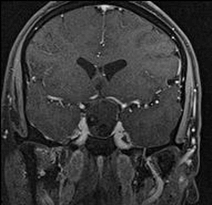

Case 2: 35/ M

- Pre-operative sagittal contrast enhanced T1W image shows a sellar mass with suprasellar extension (Figure 4)

- Intra-operative MRI (Figure 5) shows residual enhancing tumour, which was then taken up again for resection. Post operative MRI (Figure 6) shows a thin enhancing capsule with no residual tumour.

Figure 4

Figure 5

Figure 6